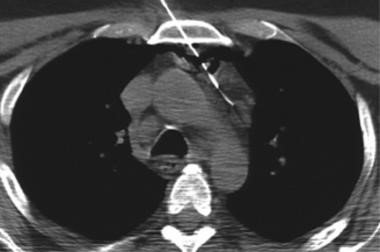

YBV sindromunu dəqiqləşdirmək üçün boş venanın tıxanmasını təsdiq etmək lazımdır ki, bu da adətən angioqrafiya ilə mümkün olur. KT angioqrafiya ilk seçimdir (Şəkil 17) və həm tıxanmanı, həm də yerini və səbəbini dəqiqləşdirə bilir.

• KT angioqrafiyada yuxarı boş venada tıxanma (tromboz, invaziya, sıxılma)

Şəkil 17. KT. Yuxarı boş vena sindromu